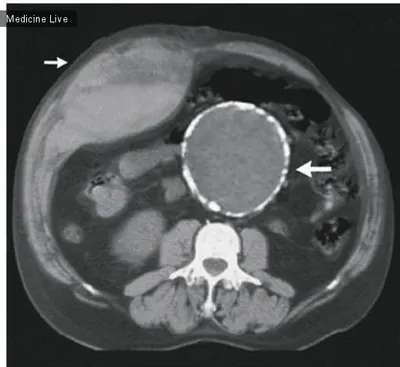

Аневризма брюшной аорты как случайная находка врачей На мужчину 56-ти лет налетел велосипедист, и удар руля пришелся в область живота. Он обратился в больницу с жалобами на вздутие и боль в этом мест

4 мар. 2026 г.

644 10 2